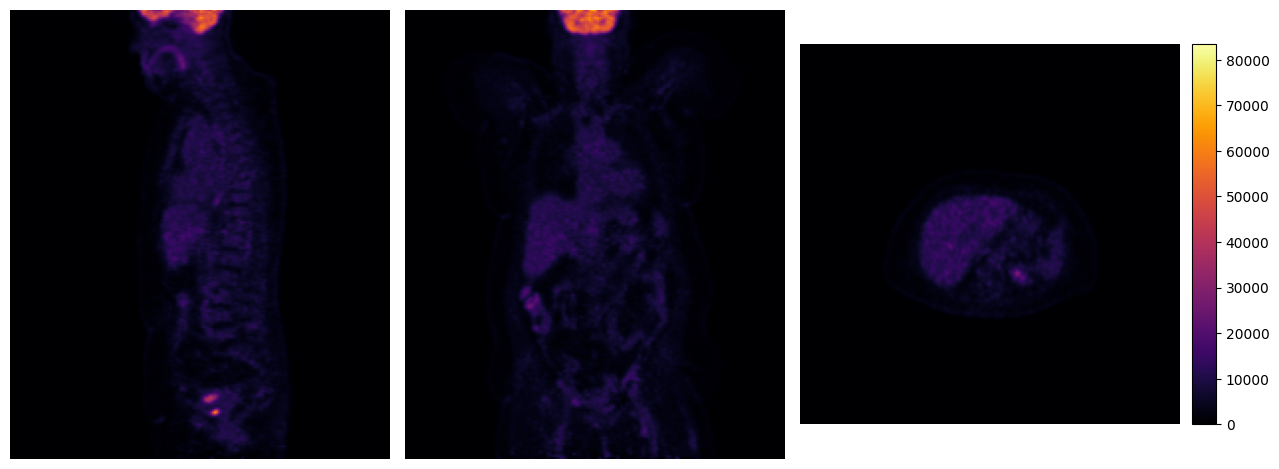

print("Original:")

mpr_plot(pet_sis[0])

print("Cropped:")

mpr_plot(cropped_pet[0])

imfusion.SharedImageSet(size: 1, [imfusion.SharedImage(FLOAT width: 160 height: 160 slices: 160 spacing: 1.5 mm)])

Cropped: